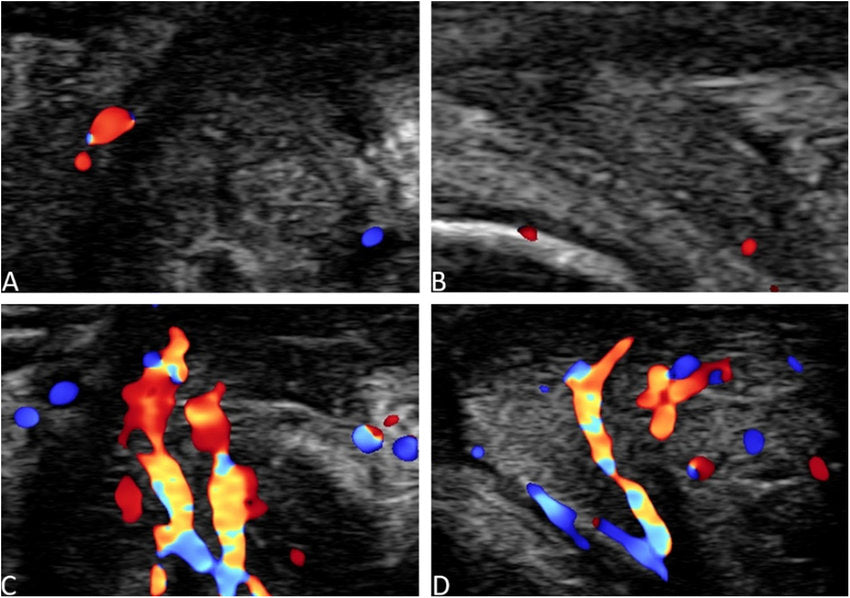

2. Clitoral Ultrasound

Clitorale echografie is een geavanceerde beeldvormingstechniek die wordt gebruikt om de structuur en functie van de clitoris in kaart te brengen. Deze methode maakt het mogelijk om veranderingen in doorbloeding en anatomie nauwkeurig te analyseren, wat essentieel is voor het begrijpen van seksuele gezondheid en eventuele disfuncties.

Door middel van deze techniek kunnen artsen en onderzoekers beter inzicht krijgen in hoe verschillende factoren, zoals hormonale veranderingen of medische behandelingen, de clitorale functie beïnvloeden.